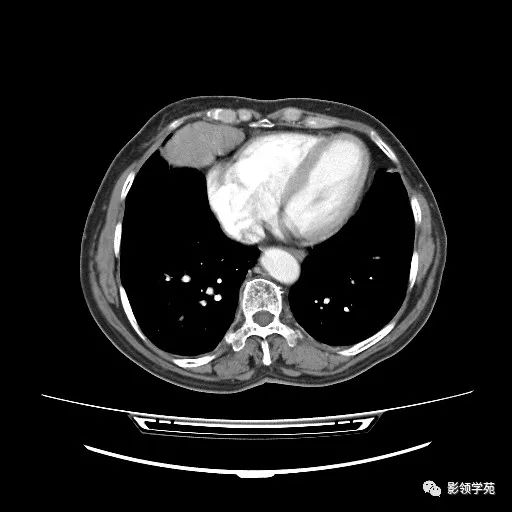

胸腺小细胞癌1例CT

女,72岁,主因进食不畅2月余,查体:T36.1℃ BP145/73mmHg,神清语利,浅表淋巴结未触及肿大,会厌稍充血、水肿,双瞳孔正大等圆,对光光反射灵敏。颈软,无抵抗。双肺呼吸音清,未闻及明显干湿性啰音,心率72次/分,律齐,心音低。腹平软,脐周无压痛,无反跳痛及肌紧张。双下肢无浮肿。四肢肌力、肌张力可。 医学百科网 | YxBaike.Com

病理结果 医学百科网 | YxBaike.Com

胸腺小细胞癌 医学百科网 | YxBaike.Com